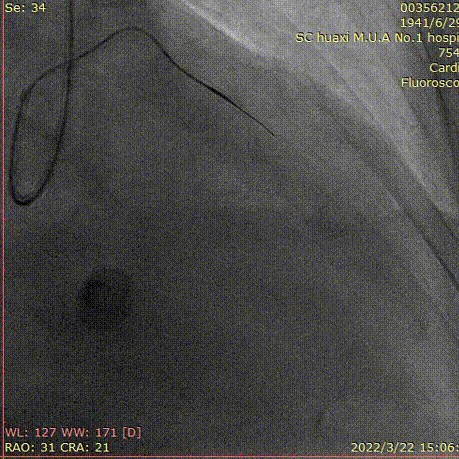

冠脉造影

造影说明:右冠近段中度狭窄,向前降支无明显侧枝。